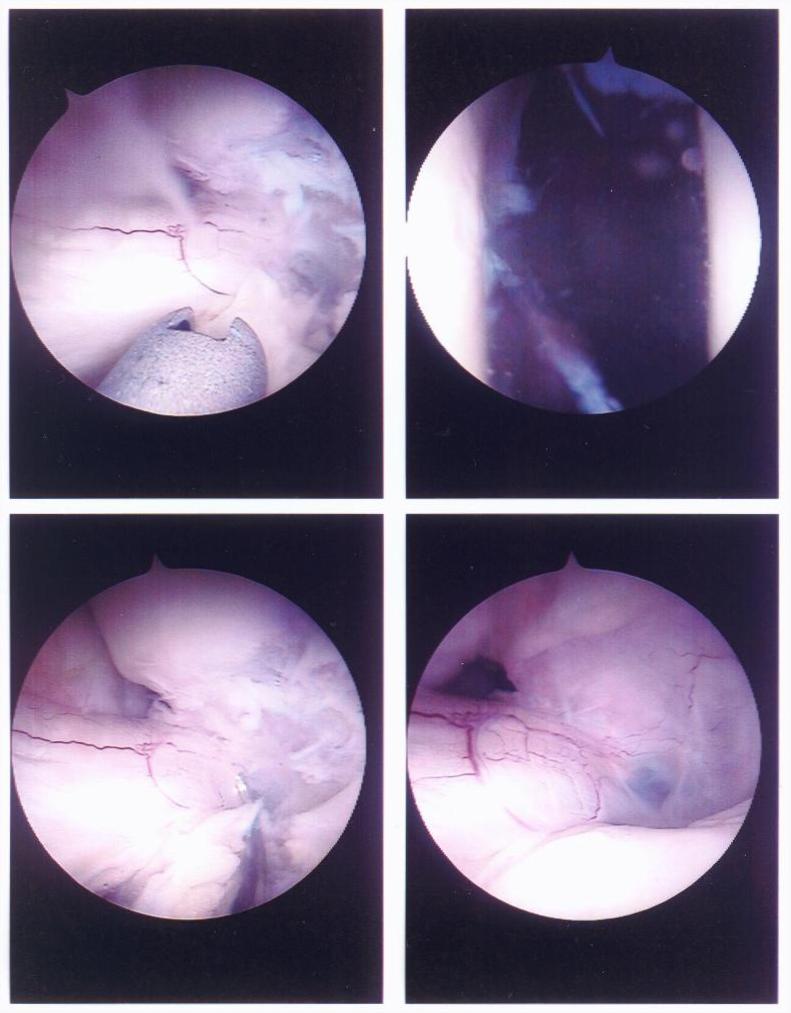

The Torn Anterior Crucial Ligament (ACL)

Here are four pictures showing the torn anterior crucial ligament (ACL).

torn ACL inside David's knee